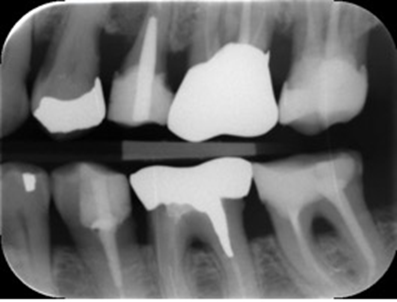

Vurder skarpheden på billedet

Acceptabel.

tandkonturer kan vurderes

approksimalflader synlige

ingen dobbeltkonturer

ingen tydelig bevægelse

let afrunding af strukturer